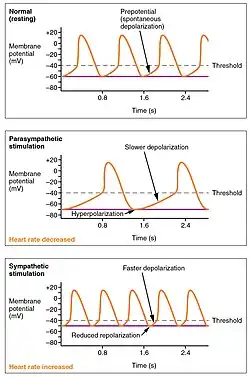

Both sympathetic and parasympathetic stimuli flow through the paired cardiac plexus near the base of the heart. The cardioaccelerator center also sends additional fibers, forming the cardiac nerves via sympathetic ganglia (the cervical ganglia plus superior thoracic ganglia T1–T4) to both the SA and AV nodes, plus additional fibers to the atria and ventricles. The ventricles are more richly innervated by sympathetic fibers than parasympathetic fibers. Sympathetic stimulation causes the release of the neurotransmitter norepinephrine (also known as noradrenaline) at the neuromuscular junction of the cardiac nerves. This shortens the repolarization period, thus speeding the rate of depolarization and contraction, which results in an increased heartrate. It opens chemical or ligand-gated sodium and calcium ion channels, allowing an influx of positively charged ions.[12]

Parasympathetic stimulation originates from the cardioinhibitory region of the brain[13] with impulses traveling via the vagus nerve (cranial nerve X). The vagus nerve sends branches to both the SA and AV nodes, and to portions of both the atria and ventricles. Parasympathetic stimulation releases the neurotransmitter acetylcholine (ACh) at the neuromuscular junction. ACh slows HR by opening chemical- or ligand-gated potassium ion channels to slow the rate of spontaneous depolarization, which extends repolarization and increases the time before the next spontaneous depolarization occurs. Without any nervous stimulation, the SA node would establish a sinus rhythm of approximately 100 bpm. Since resting rates are considerably less than this, it becomes evident that parasympathetic stimulation normally slows HR. This is similar to an individual driving a car with one foot on the brake pedal. To speed up, one need merely remove one's foot from the brake and let the engine increase speed. In the case of the heart, decreasing parasympathetic stimulation decreases the release of ACh, which allows HR to increase up to approximately 100 bpm. Any increases beyond this rate would require sympathetic stimulation.[12]